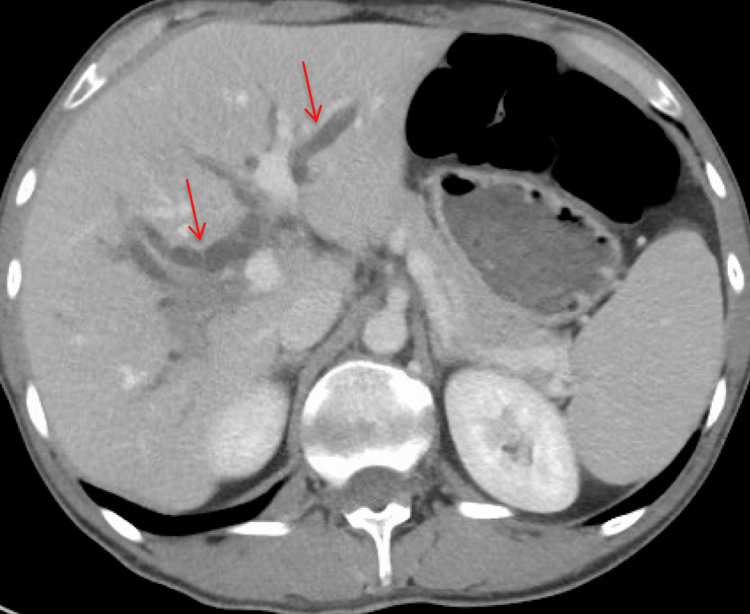

On physical examination, the patient was afebrile with stable vital signs. Laboratory investigations are shown in Table 1. A CT scan of the abdomen and pelvis identified diffuse intra and extrahepatic biliary ductal dilation without obstructing stone or mass (Figure 1).

Post-procedure, the patient developed improved jaundice and abdominal pain and was able to tolerate a regular diet with discharge home on the fifth post-procedure day. He re-presented three weeks later due to progressive cramping abdominal right upper quadrant (RUQ) pain, nausea, and bilious emesis. An abdominal ultrasound and CT demonstrated a large 8.5 cm liver abscess in the right hepatic lobe, with a posterior defect in the hepatic margin of the gallbladder wall (Figures 4–6). There was noted septic thrombosis of the right portal venous system. He underwent emergent CT-guided percutaneous transhepatic drainage of the liver abscess, with cultures demonstrating Streptococcus anginosus. He was initiated on empiric IV piperacillin-tazobactam, followed by a transition to a four-week course of oral amoxicillin-clavulanate 875-125 mg twice daily after sensitivity results were completed. He was initiated on therapeutic enoxaparin followed by conversion to oral apixaban for a planned six-month course for portal thrombosis. Repeat CT imaging demonstrated stable portal thrombus without extension or enlarging hepatic abscess. He was discharged home with planned interval endobiliary stent removal and delayed interval cholecystectomy. No complications or recurrent symptoms were observed during the patient’s follow-up after discharge.